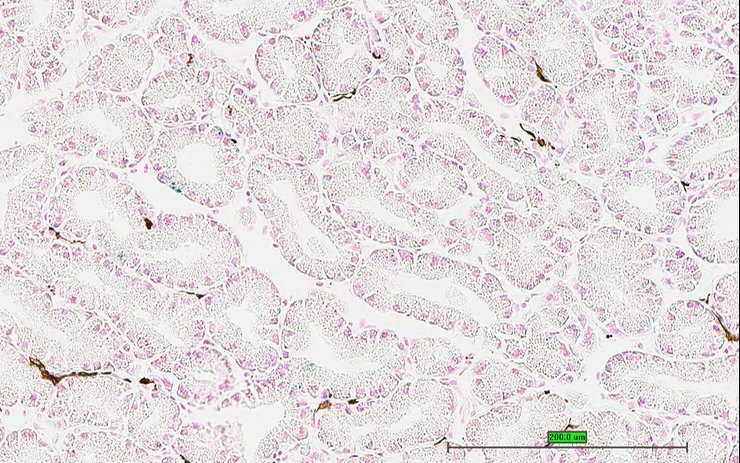

Specimen UC Davis_1879371: postnatal adult; Cacybptm1b(EUCOMM)Wtsi/Cacybp+ (more )

TS28: metanephros Present UC Davis_1879371 kidney

TS28: metanephros Present UC Davis_1879372 kidney

TS28: metanephros Present UC Davis_1879364 kidney